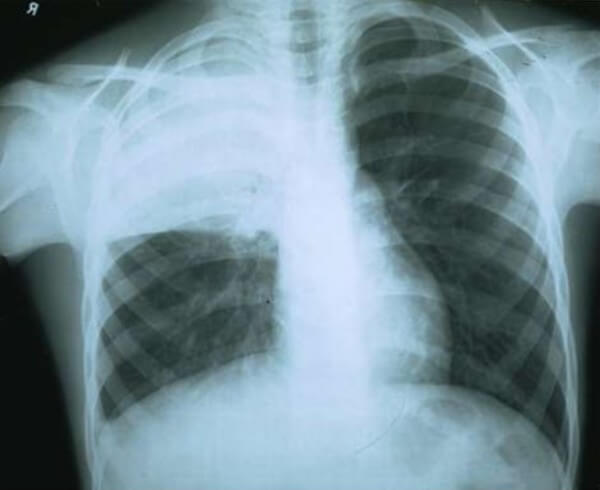

Правосторонняя крупозная пневмония на рентгене

Чаще всего крупозная пневмония возникает с какой-то одной стороны легких, а двусторонняя – редко. Классическая форма охватывает одну из долей легкого, но встречается это крайне редко, обычно поражается только один или несколько сегментов доли.

- центральная (воспаление происходит в глубоких отделах легкого, потому для диагностики обязательно нужна рентгенограмма)